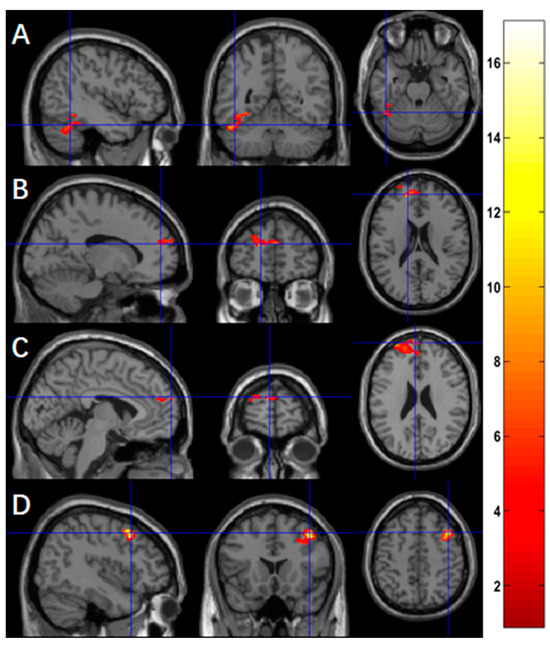

Using ASL fMRI with a voxel-level p-value of 0.005, we found a significantly negative association between practice time and the changes of activation in four clusters, mainly in the left fusiform (p = 0.027, Figure 2A) for the contrast of ‘X’, in the left superior frontal region for the contrast of ‘O’ (p = 0.008, Figure 2B), in the left superior frontal region for the contrast of ‘X+O’ (p = 0.012, Figure 2C), and in the right middle frontal region (p = 0.044, Figure 2D) for the contrast ‘X−O’. Table 3 summarizes the statistics of these significant clusters.

Figure 2.

Using ASL fMRI (n = 9), more practice time was associated with reduced functional activation in (A) the left fusiform for the contrast of ‘X’, (B) the left superior frontal region for the contrast of ‘O’, (C) the superior frontal region for the contrast of ‘X+O’, and (D) the right middle frontal regions for the contrast of ‘X−O’.